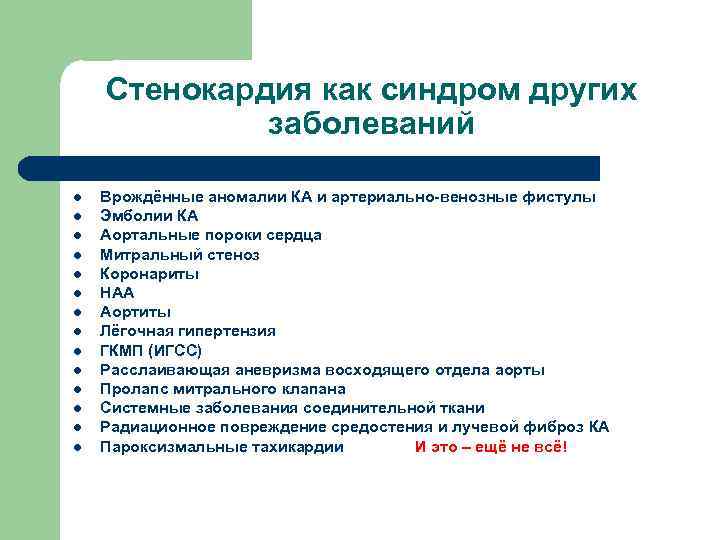

Стенокардия как синдром других заболеваний l l l l Врождённые аномалии КА и артериально-венозные фистулы Эмболии КА Аортальные пороки сердца Митральный стеноз Коронариты НАА Аортиты Лёгочная гипертензия ГКМП (ИГСС) Расслаивающая аневризма восходящего отдела аорты Пролапс митрального клапана Системные заболевания соединительной ткани Радиационное повреждение средостения и лучевой фиброз КА Пароксизмальные тахикардии И это – ещё не всё!